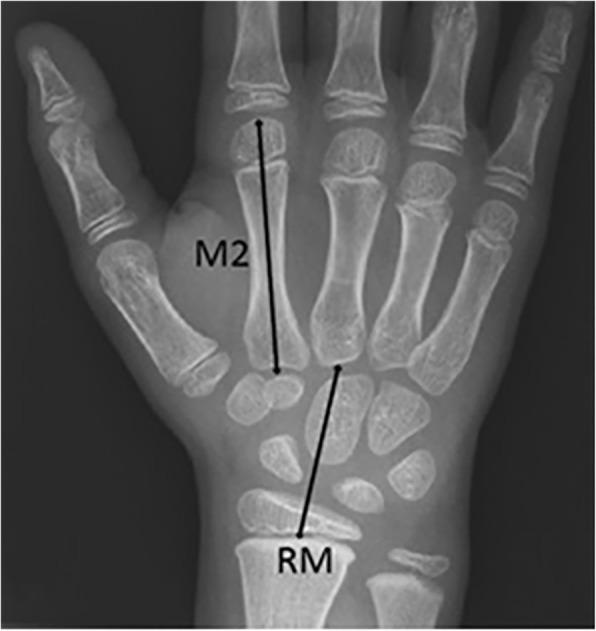

Patients with JIA participating in the BeSt-for-Kids-study, randomized to 3 treatment strategy arms, were eligible if at least 1 conventional wrist-radiograph was available. Bone damage as reflected by carpal length was assessed using the Poznanski-score. The BoneXpert-method was used to determine the Bone Age (BA, > 5 years) and bone mineral density (BMD) of the wrist. These scores were evaluated over time and compared between the treatment arms and mean JADAS10-score using linear mixed models corrected for age and symptom duration.

方法